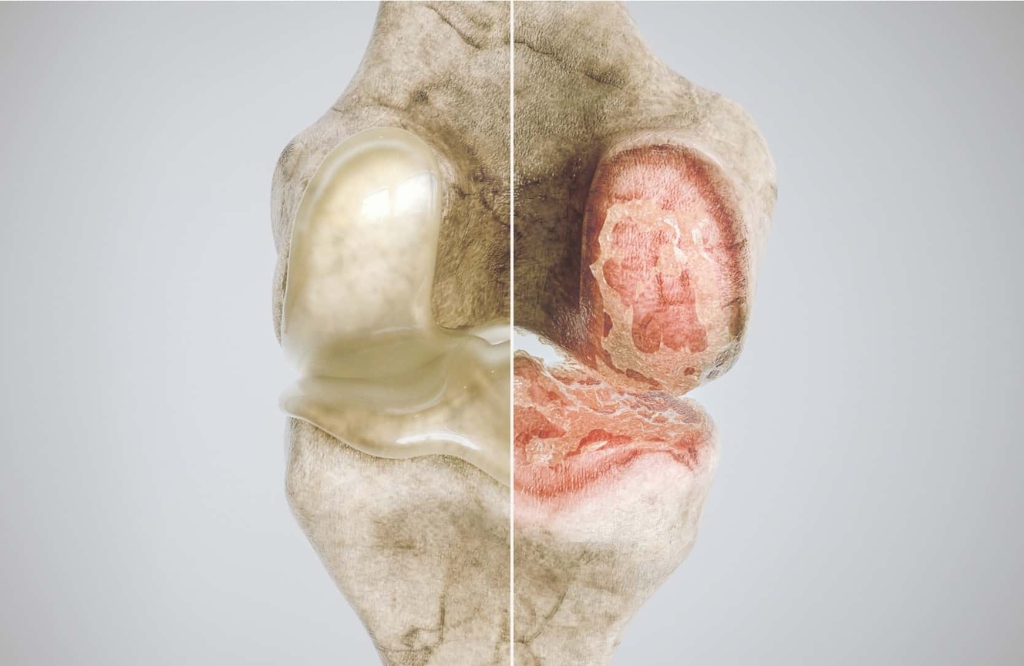

A artrose é uma condição degenerativa das articulações que causa dor, rigidez e limitações nos movimentos. Com o passar do tempo, a cartilagem que reveste as articulações vai se desgastando, comprometendo a mobilidade e causando desconforto nas atividades diárias. Esse problema é comum em pessoas com mais de 50 anos, mas também pode afetar pessoas mais jovens devido a lesões ou predisposição genética.

A artrose pode afetar diversas articulações do corpo, como os joelhos, quadris, coluna e mãos, dificultando o simples ato de caminhar, subir escadas ou até segurar objetos. O tratamento adequado pode ajudar a controlar os sintomas, retardar a progressão da doença e melhorar a qualidade de vida do paciente.